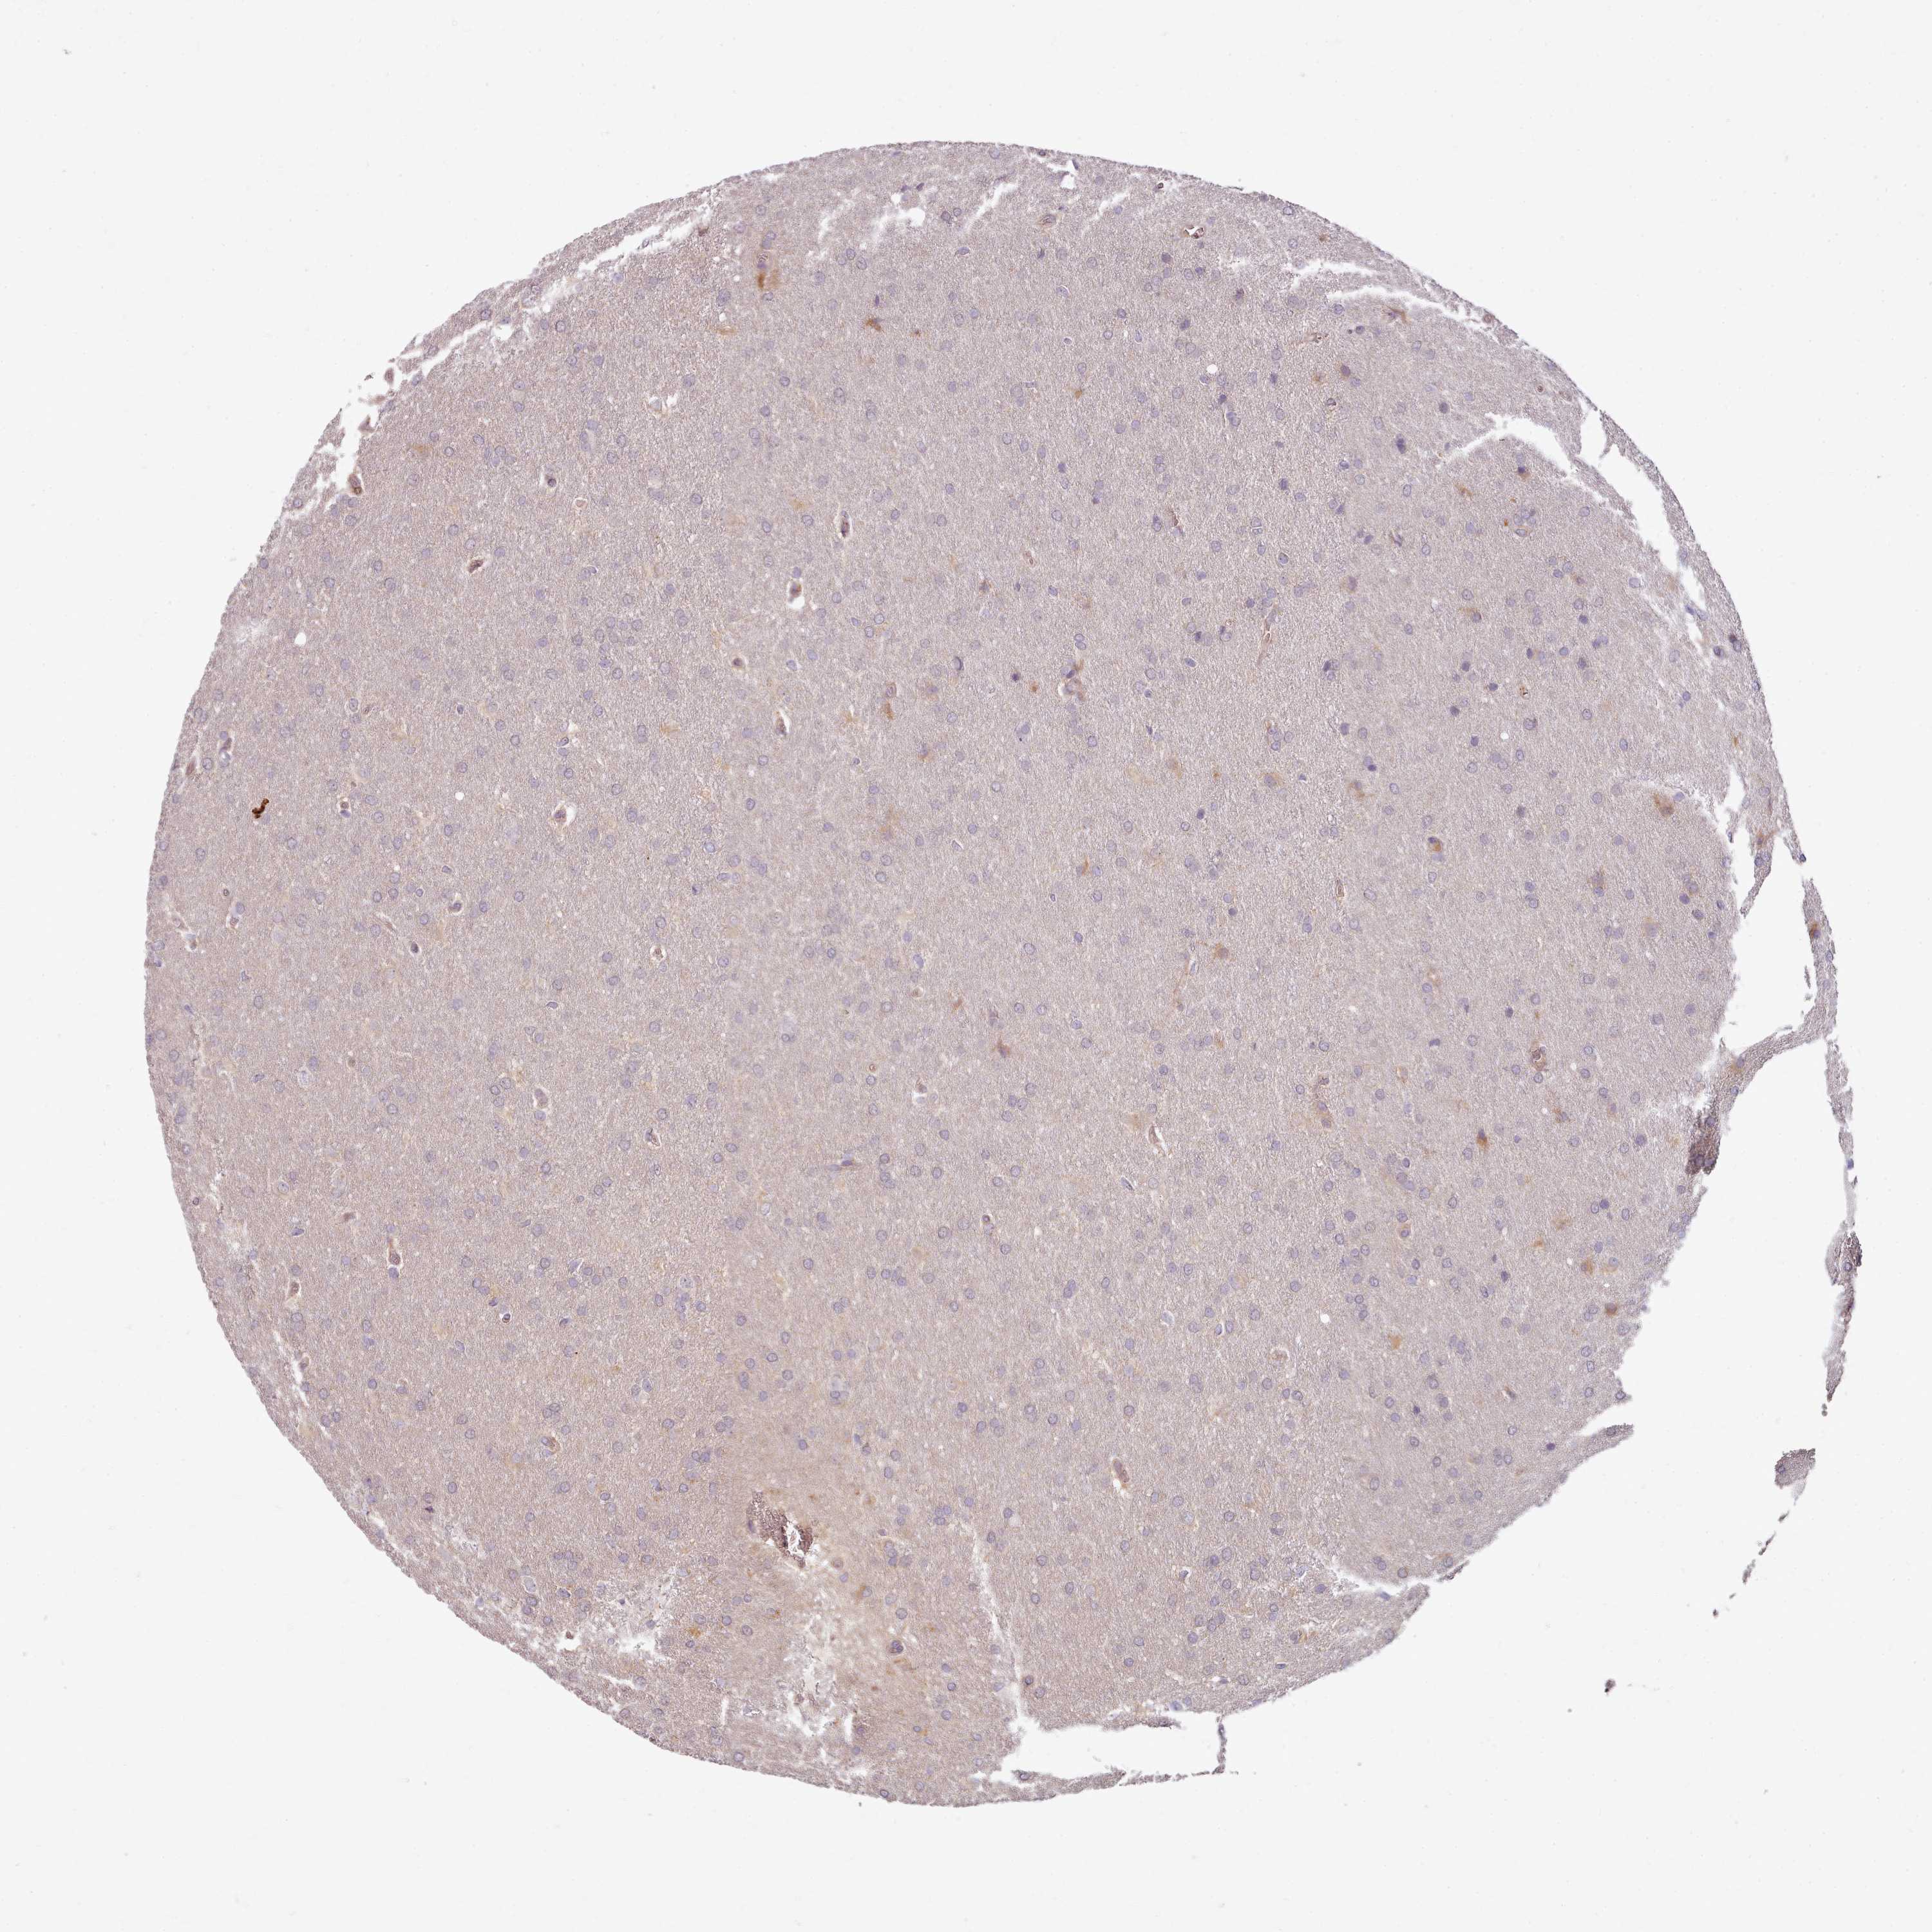

GLIOMA - Protein expressioni

A mouse-over function shows sample information and annotation data. Click on an image to view it in a full screen mode. Samples can be filtered based on level of antibody staining by selecting one or several of the following categories: high, medium, low and not detected. The assay and annotation is described here.

Note that samples used for immunohistochemistry by the Human Protein Atlas do not correspond to samples in the TCGA dataset.

Antibody stainingi

Antibody staining in the annotated cell types in the current human tissue is reported as not detected, low, medium, or high, based on conventional immunohistochemistry profiling in selected tissues. This score is based on the combination of the staining intensity and fraction of stained cells.

Each image is clickable and will lead to virtual microscopy that enables deeper exploration of all samples and also displays staining intensity scores, fraction scores and subcellular localization as well as patient and tissue information for each sample.

Antibody HPA038604

Antibody CAB025607

Glioma, malignant, High grade

Glioma, malignant, Low grade